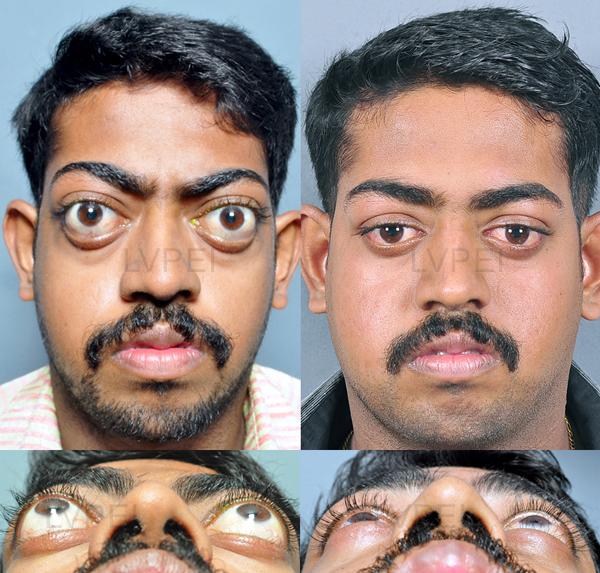

13. Orbital box osteotomy

(Done on deformed patients only)

13. Orbital box osteotomy

(Done on deformed patients only)